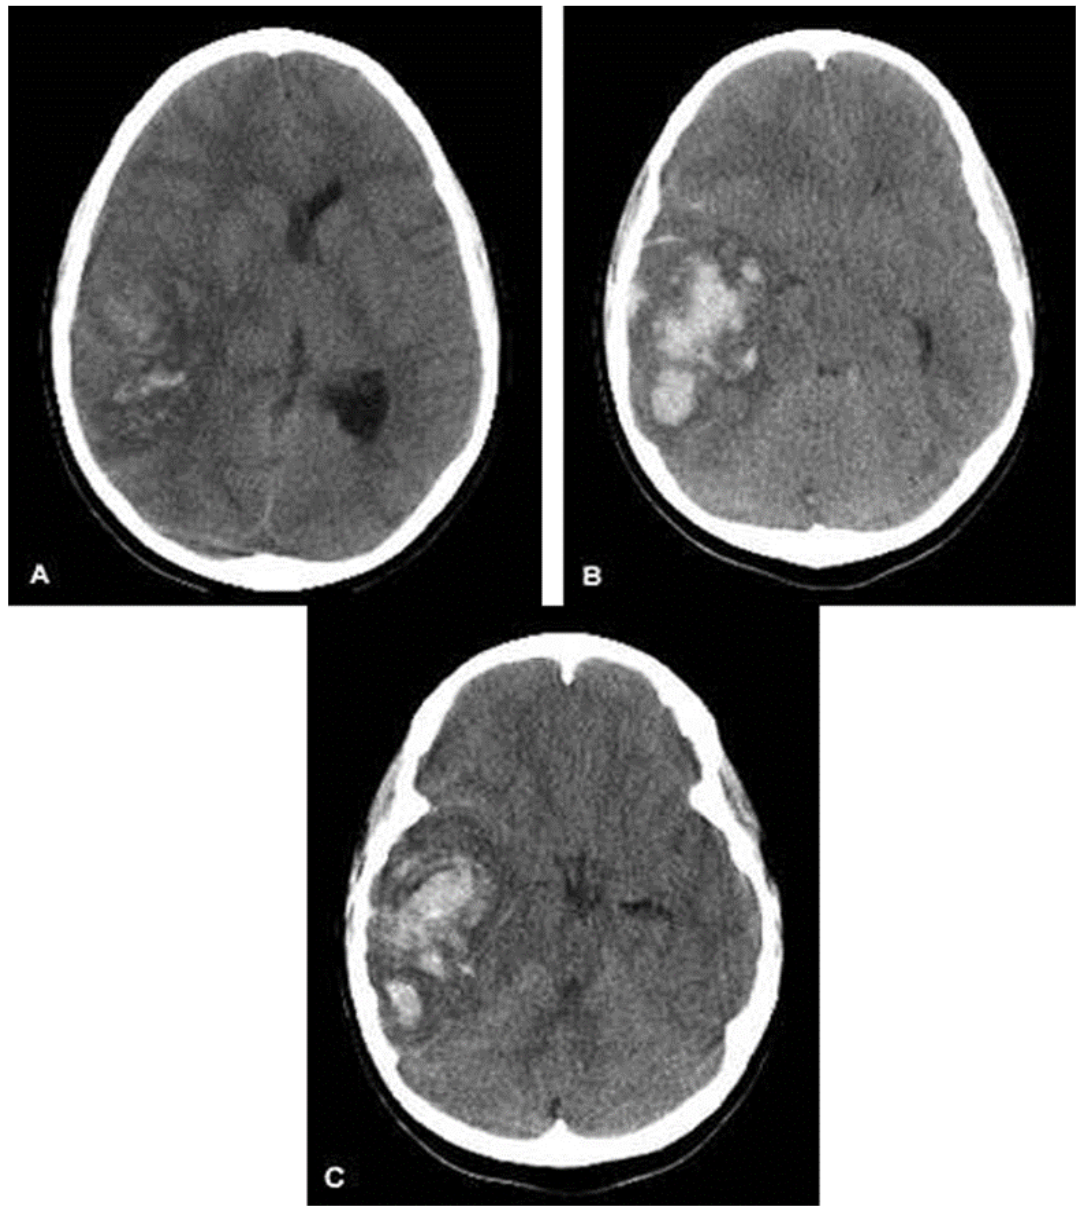

Intracranial Hemorrhage

Children with intracranial hemorrhage may present with a variety of symptoms, including headaches, frequent vomiting, and altered mental status. Intracranial hemorrhage should be suspected in any patient presenting to the ED with decreased level of consciousness. There are four types of intracranial hemorrhage:

- Epidural Hematomas: Occur when there is bleeding into the space between the skull and the dura mater. CT scan will show a convex, lens-shaped collection of blood. Blood generally does not cross suture lines. Many of these hemorrhages are caused by laceration of the middle meningeal artery, although venous bleeds can also occur. The classic presentation is a brief loss of consciousness with the trauma, followed by a lucid period and then deterioration. As epidural hematomas can accumulate rapidly, patients may change quickly and a timely diagnosis and neurosurgical intervention are key.

Figure: Epidural hematoma. Image courtesy of Jpogi. Image used under the Creative Commons Attribution-Share Alike 3.0 Unported License.

- Subdural Hematomas: Occur when there is bleeding into the space between the dura and arachnoid membranes. They appear as concave or crescent-shaped collections of blood on CT scan and can cross suture lines. These are generally caused by tears to the bridging veins between the cortex and venous sinuses. The hemorrhage occurs more slowly than in epidural hematomas, although still over a period of a few hours.

Figure: Subdural hematoma. Image courtesy of Dr. James Heilman. Image used under the Creative Commons Attribution-Share Alike 3.0 Unported license.

- Subarachnoid Hematomas: Occur when there is bleeding into the space between the arachnoid membrane and the pia mater that surrounds the brain.

Figure: Subarachnoid Hemorrhage. Image courtesy of Dr. James Heilman. Image used under the Creative Commons Attribution-Share Alike 3.0 Unported license.

- Intraparenchymal Hemorrhages: Occur when there is tearing of intraparenchymal blood vessels. Depending on the size, these can also cause mass effect and midline shift, and may be more difficult to manage surgically than extra-axial hemorrhages.

Figure: Intraparenchymal Hemorrhage. Image courtesy of MD Computed Tomography diagnostic team. Image used under the Creative Commons Attribution-Share Alike 3.0 Unported license.

When evaluating a CT scan with an intracranial hemorrhage, it is important to not only identify the type of hemorrhage, but also to note the size and whether the lesion is causing mass effect or midline shift.